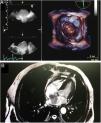

Mixoma biauricular gigante a través de comunicación interauricular

Large biatrial myxoma through an atrial septal defect